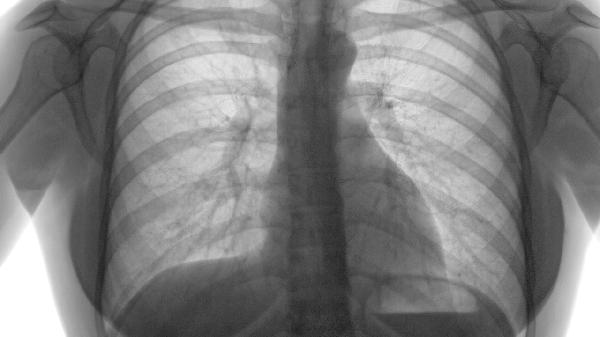

慢性支气管炎、肺结核等呼吸系统疾病迁延不愈,会持续损耗肺气。这类患者常伴有咳嗽痰多、胸闷等症状。需积极治疗原发病,可遵医嘱使用补肺汤加减等中药方剂,或玉屏风颗粒、生脉饮口服液等中成药。